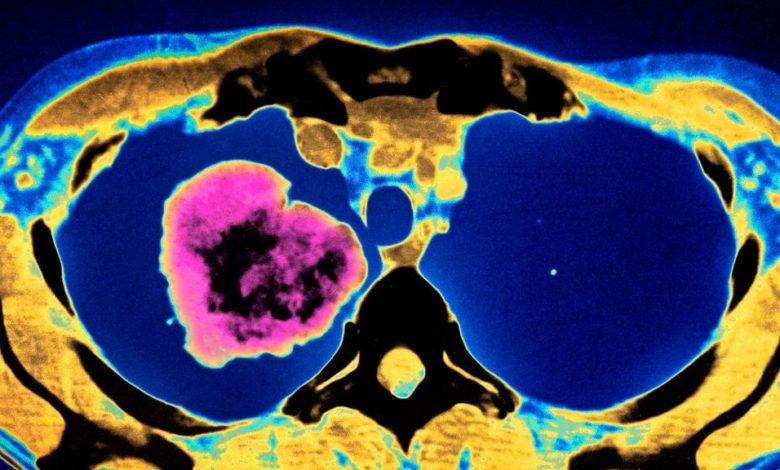

Health USAU.S. Sees Largest Cancer Death Rate Drop Ever Reported in a Year

Groundbreaking cancer treatments and reduced smoking rates have led to a 29% decline in cancer mortality since 1991 – saving around 2.9 million lives today in comparison with the mortality rate staying constant.

Among the significant advances helping to reduce cancer mortality, new imaging technologies have helped doctors assess cancer stages and prognosis accurately, and less intrusive surgical methods have resulted in quicker recovery times.